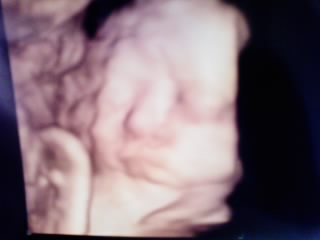

今日は朝から雨 いつもなら母親が車で病院まで送ってくれるんだけど、今日はお仕事だったので雨の中歩いて病院へ行きました。昨日、バスに乗った時にお腹を手すりにぶつけたことが気になって…。運転手さんが席に着く前に発進したもんだから、座ろうとしてた座席の手すりにガンっと当ててしまいました…その後、特に出血とか腹痛がなかったしタロちゃんも元気に動きまくってたので昨日は連絡しなかったんだけどね☆そのことを伝えると、今日は技師さんのエコー以外に先生のエコー(経腹と経膣どっちも)にNSTもと盛りだくさん☆結果、何にも問題なくて「気をつけてね~」って注意されましたそら、そうだよね…。ホント人ごみとかで歩くときは気をつけなきゃって改めて思いました。タロちゃんは 推定2500グラムになってました相変わらず、頭囲だけが週数より随分でかくて…それ以外は問題なし頚管長はまだ、しっかり4センチくらいあるので、先生からは「1日1時間くらいの運動をしてもいいよ」って言われました★なかなか、下りてきてくれなさそうな予感…明日から頑張って歩こう~今日は助産師さんの指導も受けてきたんだけど…。どぅも前回に指導が抜けてたみたいで、急いで母親クラスを受けてくださいって言われちゃった それを聞いてバースプランを提出するんだってなんか、着々と「その時」が近づいてきてる感じです♪ほんで、1つ。おっぱいのことで、たぶん赤ちゃんが吸いにくそうなおっぱいなのでおっぱいケアのことを助産師さんに相談したんだけど、そしたら「ちょっと見せて!!」って言われ…。むぎゅ~~って乳首を引っ張られた…めっちゃ痛くて「いっ痛いっ…!!」って言ったんだけど、これくらいの強さで吸われるから慣らさなきゃなんだってお風呂に入った時に毎日、これくらいはやっといてねとのこと☆んんんん~~~~~。痛い…。。。でも、タロちゃんに吸ってもらえるように頑張るかぁ~~~!!!!ホント、盛りだくさんで今日は疲れちゃいました~☆10時前に病院行って、帰ってきたら1時30分とかだったもんちょっと、休憩だよ~